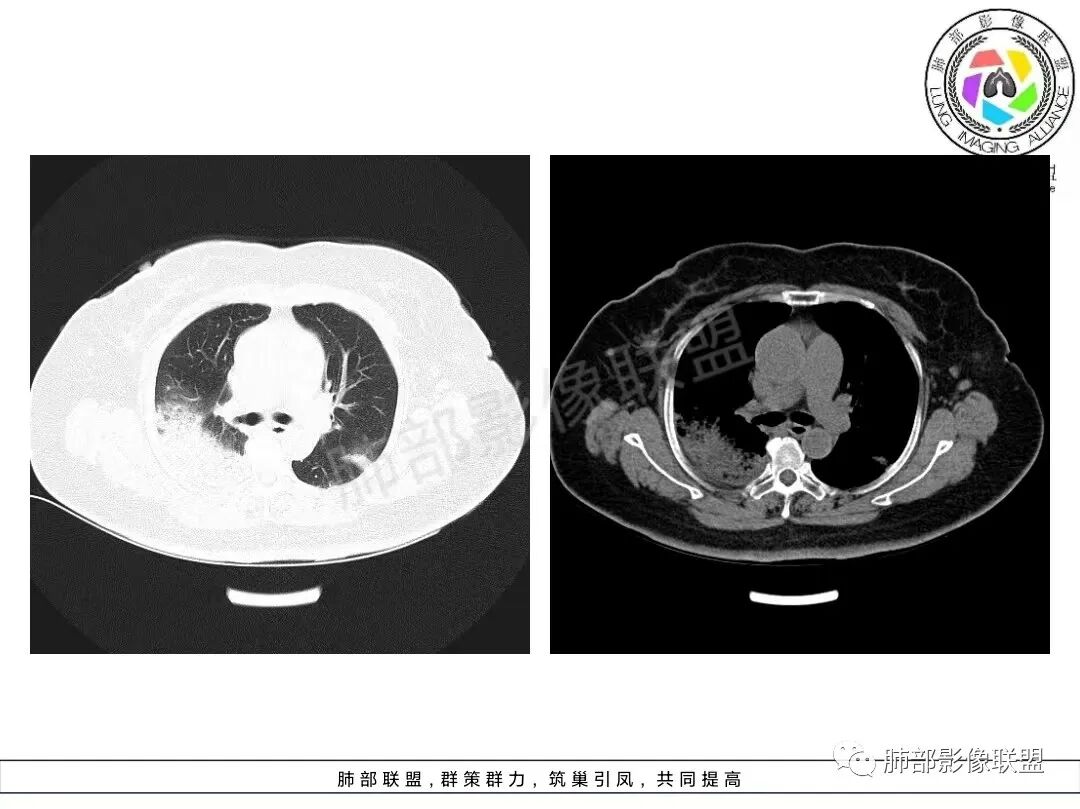

两肺沿胸膜下分布为主,大片、斑片状不均质实变,肺窗>纵隔窗,提示累及肺实质和间质,实变内充气支气管征空洞几乎不见,边缘收缩凹陷,部分平直,肺体积整体未见缩小。临床血氧降低,白细胞升高,考虑OP,COP,鉴别隐球菌,粘液腺癌!

老年女性,咳嗽、咳黄白痰,无发热,化验炎性指标高,右肺胸膜下实变,其内支气管充气、扩张,周围索条,左肺胸膜下多发结节及斑片实变,胸膜下线影,右侧少量胸水,考虑机化性肺炎,鉴别隐球菌、粘液腺癌

双肺胸膜下多发实变,边界不清,较大病变长轴与胸膜平行,近端可见充气支气管征,部分病灶内坏死边界清,胸膜下有多发相类似病灶,综合考虑首选隐球菌,其次0P尚不除外

双肺胸膜下多发斑片及大片实变影,边缘清晰,长轴平行于胸膜,部分病灶呈细网格状,右侧胸膜增厚,右侧叶间胸膜增厚,血糖高,感染指标高,考虑OP,鉴别隐球菌

2、影像特点:双肺胸膜下为主、多发斑片影、结节样实变影及磨玻璃样密度影,大部分病灶边缘平直、边界清,磨玻璃密度病灶内可见细网格影,部分病灶内可见支气管扩张表现,部分支气管直达远端,部分中断于病灶中部。部分病灶有侧向融合趋势。